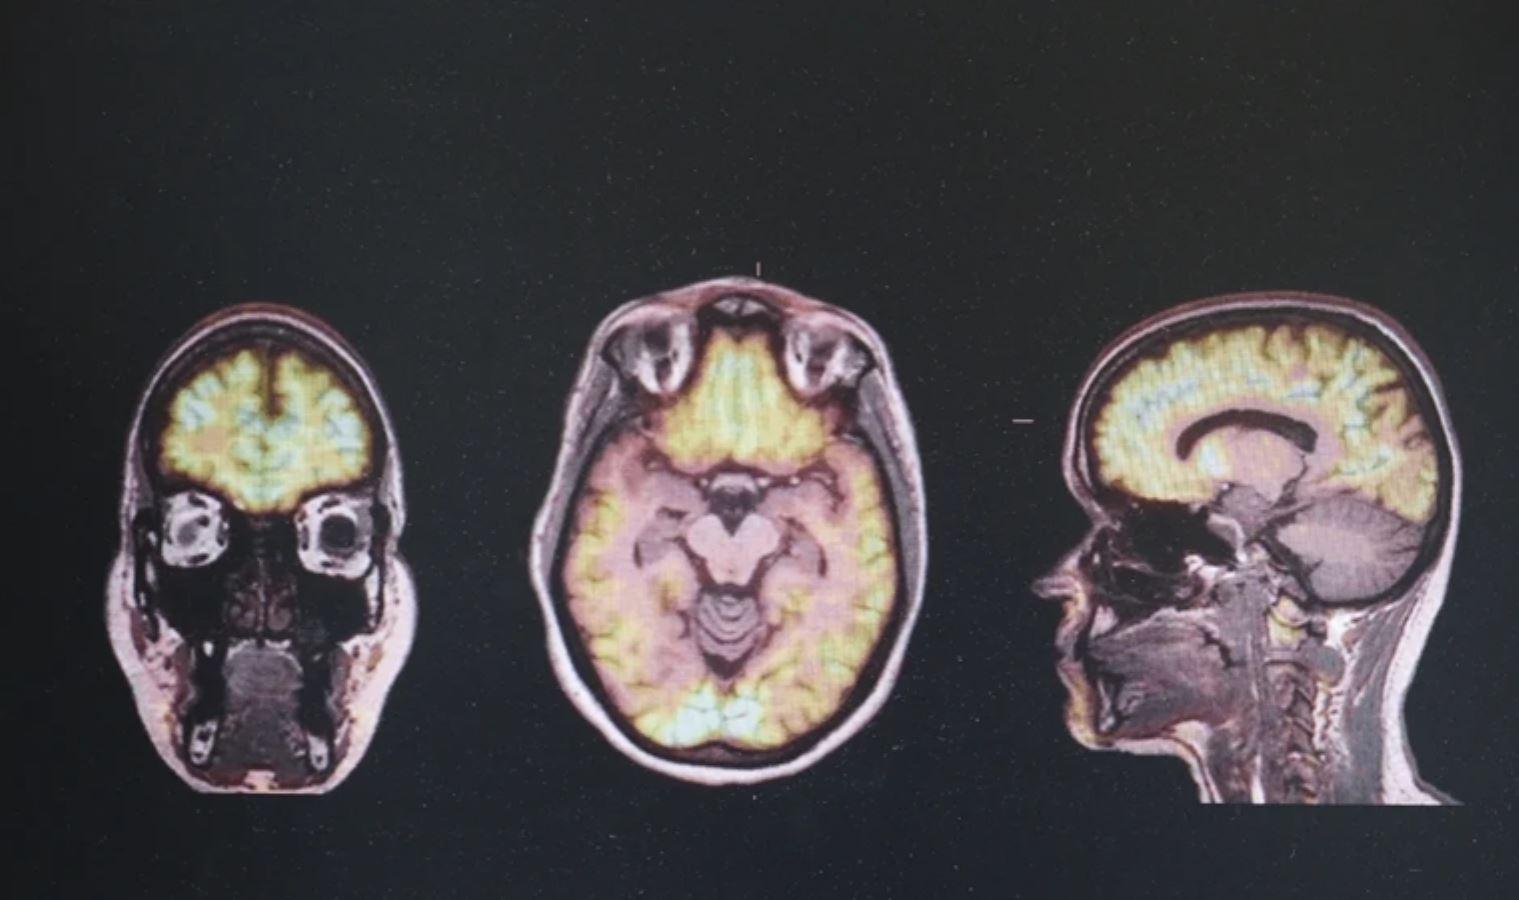

“Ben de bu hastalıkların erken teşhisinde yapay zekadan yararlanabilir miyiz diye merak etmeye başladım. Sonrasında iki arkadaşımla takım olarak, farklı faktörlerin genlerin çalışması üzerindeki etkisi olarak adlandırılan epigenetik tabanlı bir yapay zeka modeli geliştirdik. Bu modeli, söz konusu nörodejeneratif hastalıkların erken teşhisinde kullanılması amacıyla geliştirdik. Beş hastalığa odaklandık. Bunlar, frontotemporal demans, Alzheimer, Parkinson, ALS, Huntington. Bu yapay zeka modeli 5 nörodejeneratif hastalığın epigenetik tabanlarını içeriyor.”